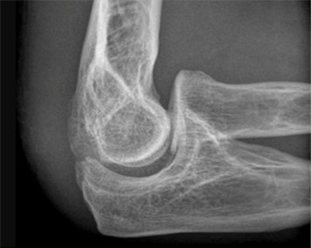

뼈 제거술 후